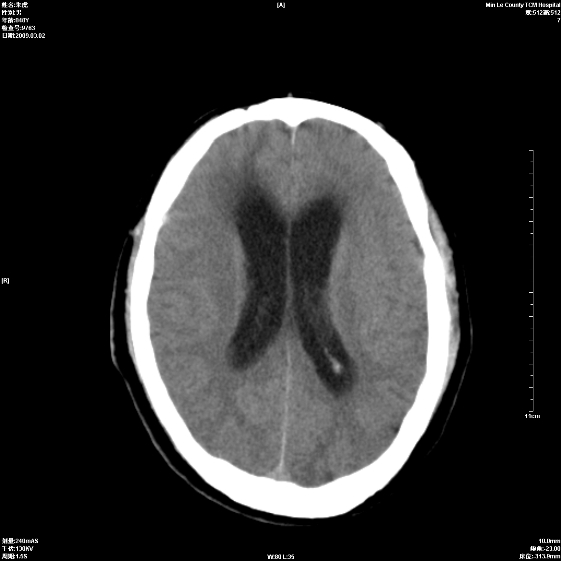

标题: CT18444:男颅咽瘤术后一月复查脑积水增多 [打印本页]

标题: CT18444:男颅咽瘤术后一月复查脑积水增多

梗阻性脑积水。

右额叶软化灶。梗阻性脑积水。

四脑室上方积水,右额叶软化灶。

1)右侧额颞部颅骨术后改变。2)右侧额颞叶脑软化灶。3)脑积水(梗阻性)。

手术后改变1、右额叶脑软化2、梗阻性脑积水。